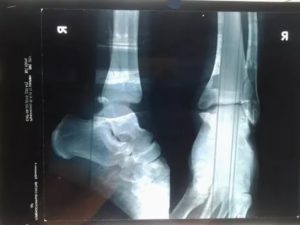

Постановка точного диагноза возможна при назначении:

- Рентгенографии пораженного сустава (применяются две проекции — боковая и передне-задняя);

После завершения процесса вновь делают рентгеновские снимки и фиксируют ногу в одном положении при помощи гипса. Гипсовую повязку придется носить на протяжении двух-трех месяцев.